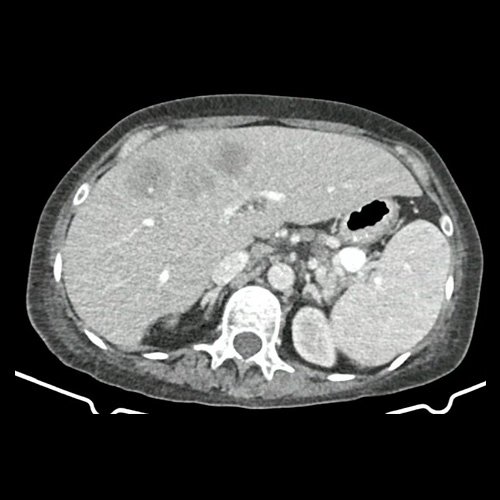

• TAC abdomen con contraste (un mes atrás): Múltiples estructuras ganglionares retroperitoneales, pre y lateroórticas, hiliares hepáticas y esplénicas aumentadas en número y de tamaño, de rango no megálico. El hígado es de forma, tamaño y situación habituales. Sus bordes son agudos. Se observa en segmento IV a –IVb, una lesión nodular hipodensa, ligeramente heterogénea, subcapsular, de bordes parcialmente definidos, con tendencia a homogeneizar con respecto al parénquima adyacente en fase de equilibrio. Mide 5,3 cm CC x 4 cm DT  x 3,7 cm AP. Hallazgos que podrían corresponder en primera instancia secundarismo hepático sin poder descartar otras etiologías. La vía biliar intra y extrahepática es de calibre conservado. La vesícula biliar es de forma, tamaño y situación normales, sin imágenes que sugieran la presencia de litiasis. Tener en cuenta que este método puede pasar por alto litiasis colesterínicas. Esplenomegalia homogénea. El eje esplenoportal es de calibre y trayecto conservado. El páncreas es de características normales. El conducto de Wirsung es de calibre conservado. Las glándulas adrenales son normales. Ambos riñones son de forma, tamaño y situación habituales. Sin evidencia de alteraciones calicopiélicas ni ureterales. La aorta, las arterias ilíacas primitivas, internas, externas y femorales, son de calibre y trayecto conservado. Trombos murales y calcificaciones parietales aortoiliacas. La vena cava inferior y las venas ilíacas primitivas, internas, externas y femorales son de calibre y trayecto conservados. Aisladas formaciones diverticulares en colon sigmoides, sin cambios inflamatorios al momento del examen. La vejiga escasamente replecionada, sonda balón en su interior. El útero es de forma, tamaño y situación conservada, en AVF, sin alteraciones densitométricas. No se observan alteraciones en topografía anexial. No se observa líquido libre ni neumoperitoneo Flebolitos pelvianos.

• TAC de abdomen y pelvis CC EV - informe preeliminar (Dia 30): En esta ocasión se observa hepatomegalia. Sus bordes son agudos. Continúa visualizándose de mayor tamaño, involucrando a casi la totalidad del segmento IV, una lesión nodular, de márgenes irregulares, hipodensa, ligeramente heterogénea, subcapsular, de bordes parcialmente definidos, Mide 9 cm CC x 6.5 cm DT x 5 cm AP (antes medía 5,3 cm CC x 4 cm DT x 3,7 cm AP). Actualmente se observa otra lesión nodular adyacente a la anterior descripta, en el segmento IVa/VIII, de similares características, que mide 3.5 cm DT x 3 cm AP, y otra en segmento IVa/II que mide 3 cm CC x 1.5 cm DT x 1 cm AP. Además se destacan otras dos lesiones, con similares características que las previas descriptas en segmento II que mide 19 mm DT x 15mm AP y en segmento VI que mide 14mm DT x 17mm AP. Hallazgos que podrían corresponder a secundarismo vs proceso infeccioso. Cotejar con datos clínicos de la paciente. Múltiples estructuras ganglionares retroperitoneales, pre y lateroórticas, hiliares hepáticas y esplénicas aumentadas en número y de tamaño, destacándose, en actual estudio,  una preaórtica derecha que mide 10 mm en su eje corto. En base pulmonar derecha se observan múltiples formaciones nodulares sólidas, irregulares, que realzan de manera heterogénea tras las administración de contraste E.V, como así también se observa otra de similares características en pulmón izquierdo en contacto con pericardio, la cual es la de mayor tamaño y mide 19 mm DT x 17mm AP. Hallazgos que obligan a descartar secundarismo pulmonar. Leve derrame pleural derecho. Hallazgos no visualizados en TC previa. Esplenomegalia que muestra densidad discretamente heterogénea, con algunas zonas de hiporrefuerzo de aspecto nodular. Trombos murales y calcificaciones parietales aortoiliacas. Aisladas formaciones diverticulares en colon sigmoides, sin cambios inflamatorios al momento del examen. Pequeña hernia inguinal epiploica izquierda, sin complicaciones agudas al momento del examen. Flebolitos pelvianos. Granuloma calcificado en TCS del glúteo izquierdo que mide 14mm. No se identifican alteraciones en las estructuras óseas visualizadas. Lesión osteoblásticas en cuerpo vertebral de L2.

TAC de abdomen y pelvis (internación previa)

TAC de abdomen y pelvis (Dia 30)